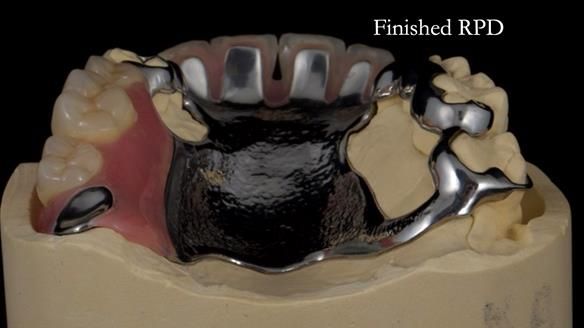

Keith’s case was one of the most challenging and rewarding cases I’ve treated this year. This 64 year old man presented with ill-fitting acrylic partial dentures that lacked stability, retention, and aesthetics. They constantly broke. He had lost the upper front teeth in a road traffic accident in his early 20s. The unopposed teeth had erupted, taking up space. After careful planning, we made a durable, metal-based upper partial denture/splint to address his dental concerns. He loved the outcome.

1. Denture design: A custom cobalt-chromium framework was Scandinavian-designed to maximise stability, protect the remaining teeth, and allow for future additions if needed.

Keith’s denture incorporated a Duracetal shell clasp on upper right first premolar (Myerson), which are designed to be virtually visible, providing a more aesthetic solution while enhancing patient comfort. The Scandinavian-inspired approach, based in modern removable prosthodontic techniques, ensured the denture was not only durable but also visually pleasing. Additionally, the design was carefully planned to allow for future modifications, ensuring that if Keith loses additional teeth, the denture can be adapted rather than replaced entirely.